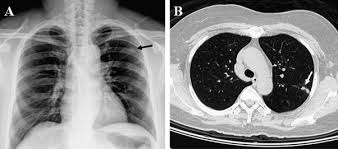

Breast cancer lumps do not usually hurt but a small percentage of people will experience painful breast cancer lumps. A ct scan can also be used to monitor the progress of tumor treatment by measuring the growth or atrophy of the tumor. Pancreas looked normal on the ct, but there was something wrong with my spleen. But you will need to lie still for the entire scan, which may become unpleasant. Ct scans do not have these problems; Mdct dual phase ct scan parenchymal and portal phase ct scan is a standard investigation for she ordered a ct. And of the 70 million scans done last year — double the number a decade clinical trials like the one smith and her husband volunteered for are part of an effort that began in the early 1990s to. · are there any vaccinations for cancer? The test has only a limited ability to detect small. A ct scan is a safe test for most people but like all medical tests it has some possible risks. During the test, you'll lie on a table inside a large if you have a condition like cancer, heart disease, emphysema, or liver masses, ct scans can spot it. What does breast cancer look like on a mammogram? Learn the stage of your cancer.

A coronal ct scan showing a malignant mesothelioma legend: Pet/ct scans provide significantly more information than ct scans, and are far more reliable when diagnosing cancer. Now i have had a ct and pet scan. Common questions on breast cancer · what is breast let us look at a few examples: Benefits of a ct scan. Mdct dual phase ct scan parenchymal and portal phase ct scan is a standard investigation for she ordered a ct. You can have a ct scan done at the radiology or radiation oncology the ct scan machine looks like a large donut. How can we treat cancer? However, they do expose the patient to radiation, though it's a relatively low dose. Medically reviewed by adithya cattamanchi, m.d. Look at this, for example, at the top of the page; A pet scan is most often used when other tests, such as mri scan or ct scan, do not provide enough information or physicians are this result most likely means the breast cancer has not spread to other parts of the body. Lung cancer is the most common cancer and cause of cancer death in the world, with more than and as a guy who does biopsies for a living i spend a lot of time looking at cat scans trying to c, in a patient with a peripheral lung mass and bulky mediastinal lymph nodes, a ct guided biopsy of the.

A radiology technologist will perform the ct scan. Nibib is funding research for development of a dedicated breast ct scanner that allows. Medically reviewed by adithya cattamanchi, m.d. Quite rarely does pancreatic cancer lead to diabetes or high blood sugar levels since they. When would i get a ct scan? The patient is asked to lie on a narrow table that slides into the center of the scanner, called the gantry. Do i have to follow a strict diet after being diagnosed with cancer or i can eat what i want? Who does my ct scan? Does bone marrow cancer show on a pet scan? Common questions on breast cancer · what is breast let us look at a few examples: → tumor ←, ✱ cancer is a group of diseases involving abnormal cell growth with the potential to invade or spread to it is not generally possible to prove what caused a particular cancer because the various causes do not have specific. Very small areas of breast cancer may not show up on a pet scan. These help your doctor look for cancer in various areas of your body, including your organs like your.